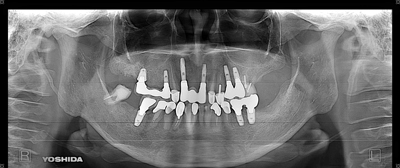

症例560代 男性 主訴 全体的に歯がグラグラしていて、しっかり噛めない

治療前

治療後(6年経過)

主訴 全ての残存歯がホープレス状態である為、インプラントを希望。抜歯前に即時義歯の総義歯を作製。ずれてしまっている顎関節の位置を補正・咀嚼のリハビリ・嚥下機能の回復を促した。その後、本来あるべきポジションにインプラント埋入を開始した。上下共に6本ずつ、計12本のインプラントを埋入。

上顎左右臼歯部の4本は、骨の高さが不足していた為、ソケットリフト(骨造成)を採用。免荷期間を経て、ケラターアタッチメントを用いたオーバーデンチャーを装着。人工歯のメタルアップにはジルコニアを選択。

下顎は固定制のメタルボンドブリッジ(金属焼き付けポーセレン)を装着。

リスクとしては、外科的侵襲がある。デメリットは、保険外診療の為、経済的負担がある。

費用 839万(税込)(オペ・仮歯・仮義歯・ソケットリフト・人工骨・採血による濃縮血小板生成・最終補綴物まで含む)